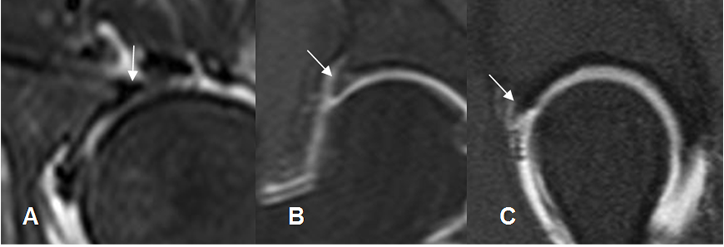

El labrum articular es una estructura triangular e hipointensa en todas las secuencias. (Fig 27 y 28).

El surco sublabral, debe diferenciarse de una ruptura del labrum acetabular. Se localiza en la parte anterosuperior o posteroinferior del acetábulo, adyacentes a la fosa acetabular. (9). Esta estructura se llena de contraste y presenta borde regulares. (Fig 29).

Fig 27. Labrum acetabular normal.

A: RM axial en T1 y B: RM coronal en T2. Estructura hipointensa en todas las secuencias, sobre el extremo de la cavidad acetabular.

Fig 29. Variante normal.

A: ArtroRM coronal y B: ArtroRM axial en STIR. Defecto en la parte anterosuperior y posterior del labrum, llenos de contraste, que corresponden al surco sublabral normal.